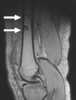

Multiple enchondromas

An enchondroma is a benign cartilage tumour found inside bones. Typically, enchondroma is discovered on an X-ray scan. [Source: Wikipedia ]